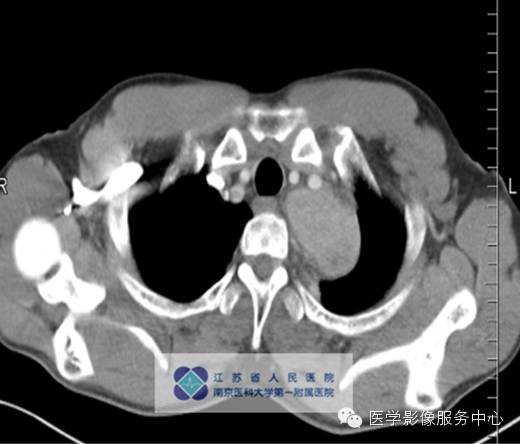

男,27岁,因“查体发现纵隔占位三月余”入院。

影像分析:左上、后纵隔内见类圆形软组织密度增高影,密度尚均匀,边缘清晰,增强扫描均匀强化。

单中心型:大部分为透明血管型,表现为纵隔及肺门圆形或卵圆形较大软组织肿块,边缘光滑锐利可有分叶,多数密度均匀可伴斑点状、树枝状等不同表现钙化。Meador等报道病变强化与病灶大小有关,小于5cm多为均匀强化,大于5cm的多不均匀强化,另外,还与病变的组织学特点如变性、坏死、纤维化的程度有关。

动脉期病灶明显强化,均匀或不均匀,其强化程度可与邻近动脉相仿;